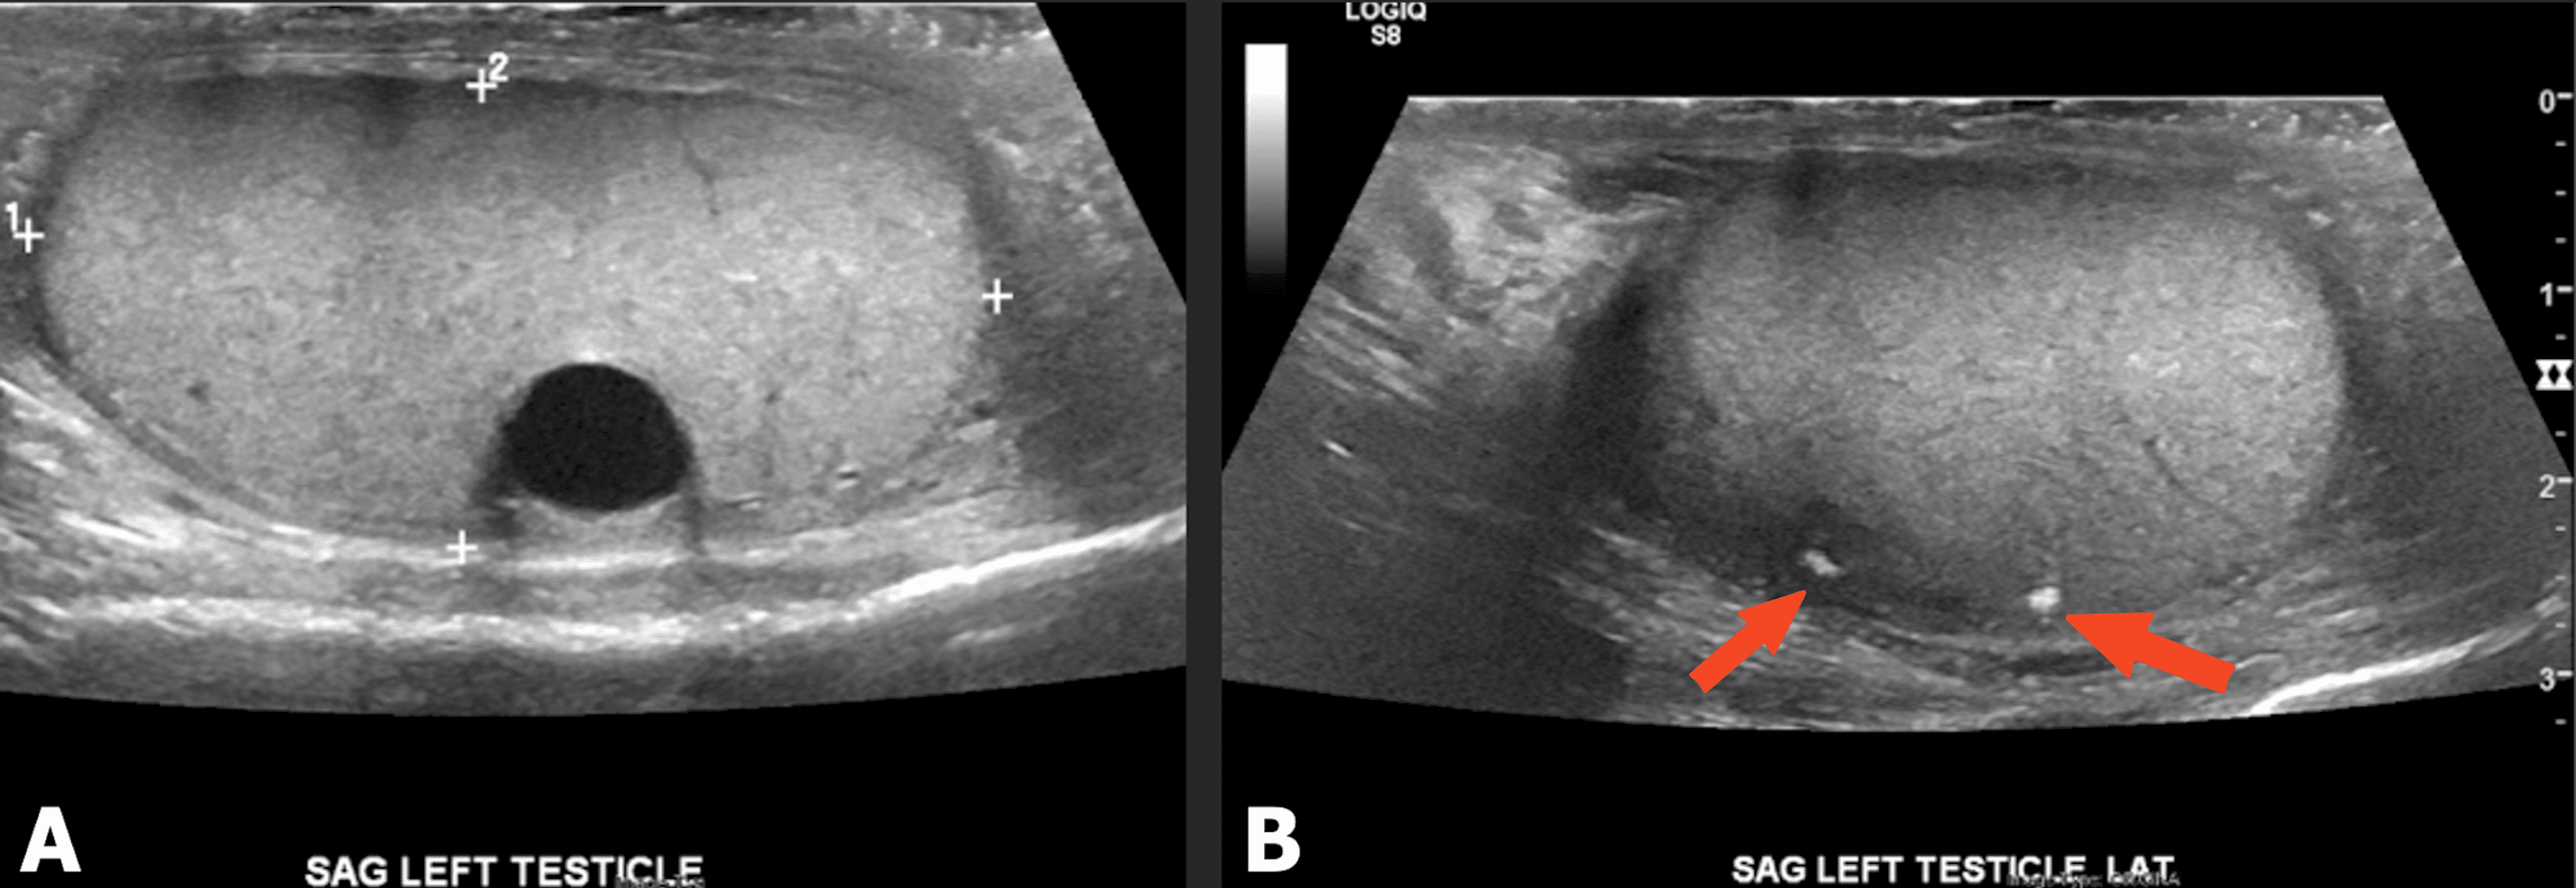

Imaging identifying the primary tumor and the brain metastasis, as well Testicular Cancer Brain Metastases Testicular cancer with neurological symptoms indicates brain metastases. Common treatments for brain metastases from testicular primary cancers include surgical resection, whole brain radiation (wbrt), stereotactic radiosurgery (srs), or combinations of these methods. Vol 397 february 27, 2021. We found that brain tumors from testicular cancer are very rare, found in just 0.4% of the patients we studied. Our study evaluated. Testicular Cancer Brain Metastases.